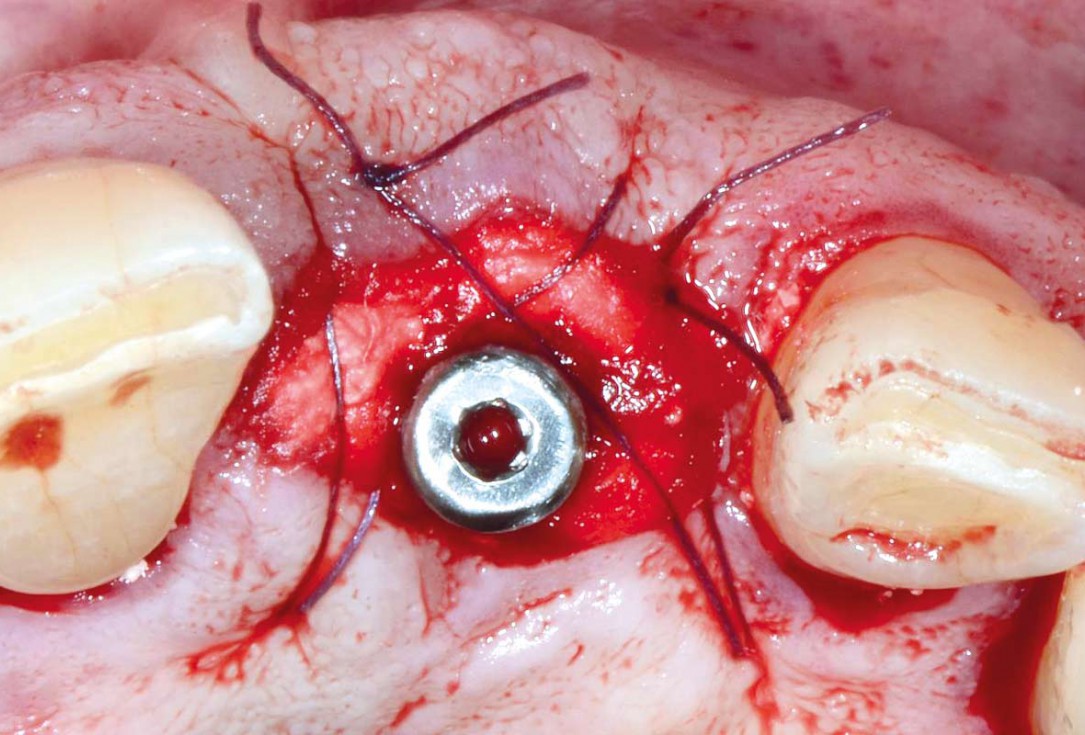

Immediate implant placement using cerabone® and collagen fleece - Dr. D. Jelušić